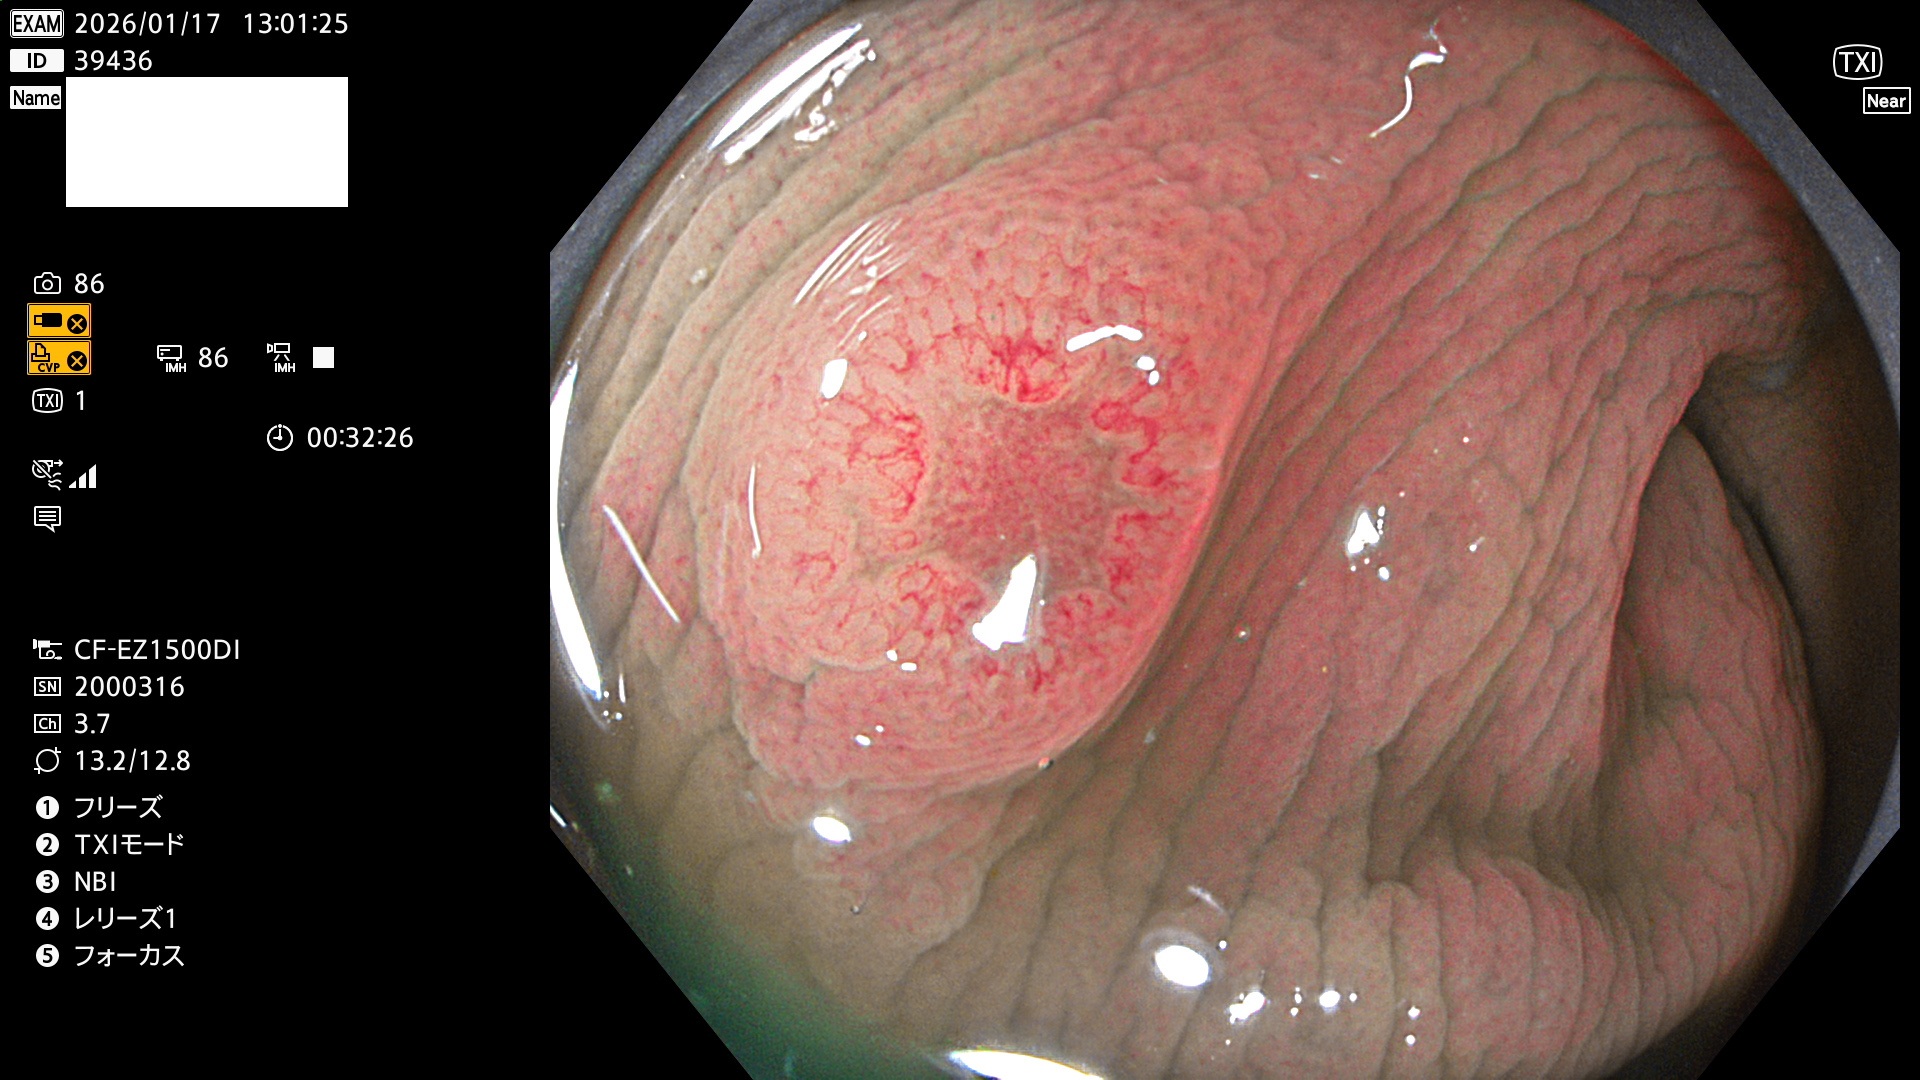

完全に平坦な物をUb、陥凹している物をUcと呼びます。Ubは認識が困難で、Ucはびらん(炎症)と紛らわしいために見落とされやすく、「内視鏡後・大腸癌」の原因になります。

毎週の検査(木・金・土・日)に発見されたUbとUc型・腺腫を、その週の日曜の夜にUPし1週間、提示します。

2026年1月15日〜1月18日の4日間(40件)5個 (Uc_ADR=5個/40人=13%)